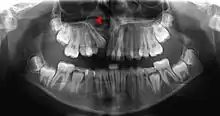

Alveolar bone loss

Bone is lost through the process of resorption which involves osteoclasts breaking down the hard tissue of bone. A key indication of resorption is when scalloped erosion occurs. This is also known as Howship's lacuna.[18] The resorption phase lasts as long as the lifespan of the osteoclast which is around 8 to 10 days. After this resorption phase, the osteoclast can continue resorbing surfaces in another cycle or carry out apoptosis. A repair phase follows the resorption phase which lasts over 3 months. In patients with periodontal disease, inflammation lasts longer and during the repair phase, resorption may override any bone formation. This results in a net loss of alveolar bone.[19]

Alveolar bone loss is closely associated with periodontal disease. Periodontal disease is the inflammation of the gums. Studies in osteoimmunology have proposed 2 models for alveolar bone loss. One model states that inflammation is triggered by a periodontal pathogen which activates the acquired immune system to inhibit bone coupling by limiting new bone formation after resorption.[20] Another model states that cytokinesis may inhibit the differentiation of osteoblasts from their precursors, therefore limiting bone formation. This results in a net loss of alveolar bone.[21]

During chronic periodontal disease that has affected the periodontium (periodontitis), localized bone tissue is also lost.

The radiographic integrity of the lamina dura is important in detecting pathological lesions. It appears uniformly radiopaque (or lighter).[8]